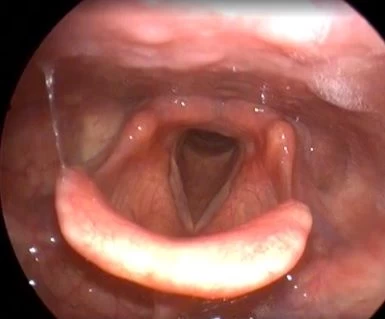

Клинический случай №5. Удаление полипа правой голосовой складки с использованием СО2-лазера.

После процедуры воспалительные изменения в области голосовой складки были практически незаметны.

Рис 5А. Полип (отечный) правой голосовой складки. Перед вмешательством.

Рис 5Б. Полип (отечный) правой голосовой складки. На 1 день после операции.